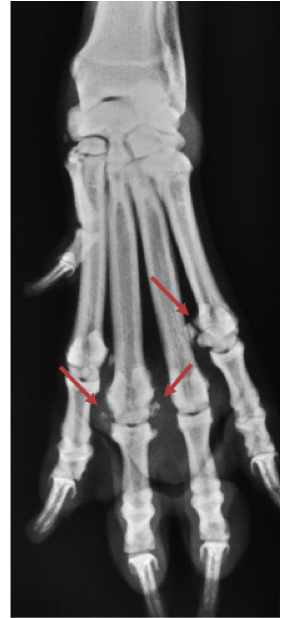

Kapotte sesambeentjes kunnen aanleiding geven voor het ontstaan van artrose in het betreffende gewricht. Los daarvan zien we met name bij de Golden Retriever, en soms ook bij andere grote rassen artrose in de gewrichtjes van middenvoetsbeenderen en tenen (zie röntgenfoto). Typisch is dat dit met name voorkomt in de middelste twee tenen, en dan ook vaak in beide ondervoeten. Overgewicht en een te lage schildklierfunctie zijn predisponerende factoren.

Röntgenonderzoek artrose, botnieuwvorming rond het gewricht, verbreding van het gewricht.